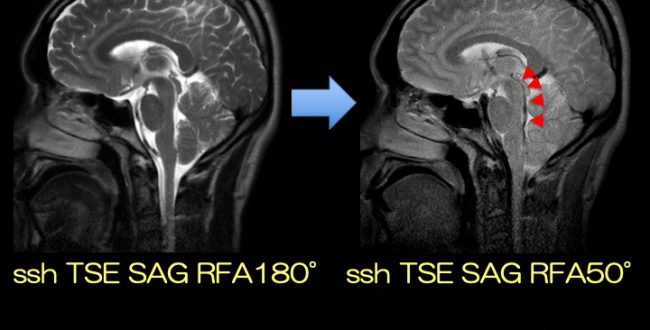

次世代のOpen Bore 3T MRIによる臨床応用 3T MRIの臨床応用。Look back Gyro cup ②「 CSF Flow with Low RFA SSTSE。次世代のOpen Bore 3T MRIによる臨床応用 3T MRIの臨床応用。